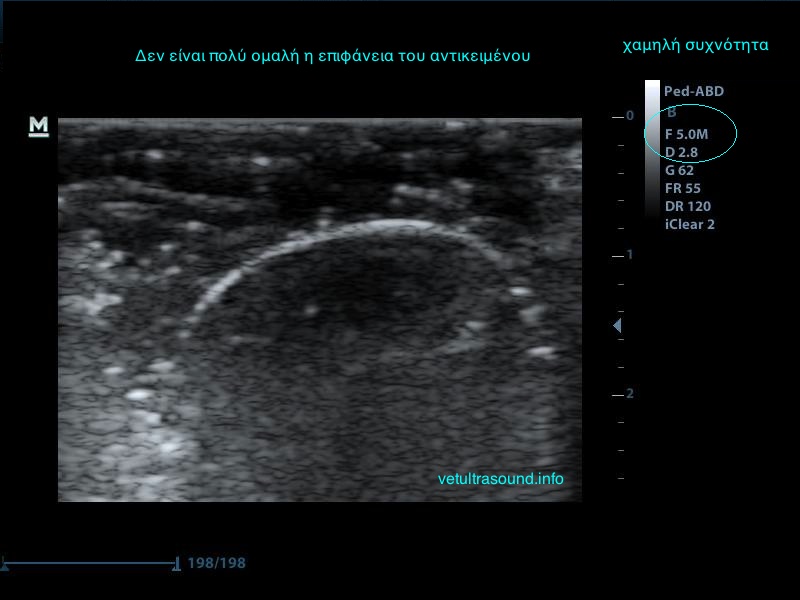

3) Τη συχνότητα, δηλαδή όσο πιο μεγάλη είναι αυτή, τόσο πιο πολλές λεπτομέρειες βλέπουμε αλλά ταυτόχρονα αυξάνονται τα τεχνουργήματα από αέρα και άλλες δομές. Οι αρμονικές βοηθούν στην καταστολή αυτών των τεχνουργημάτων.